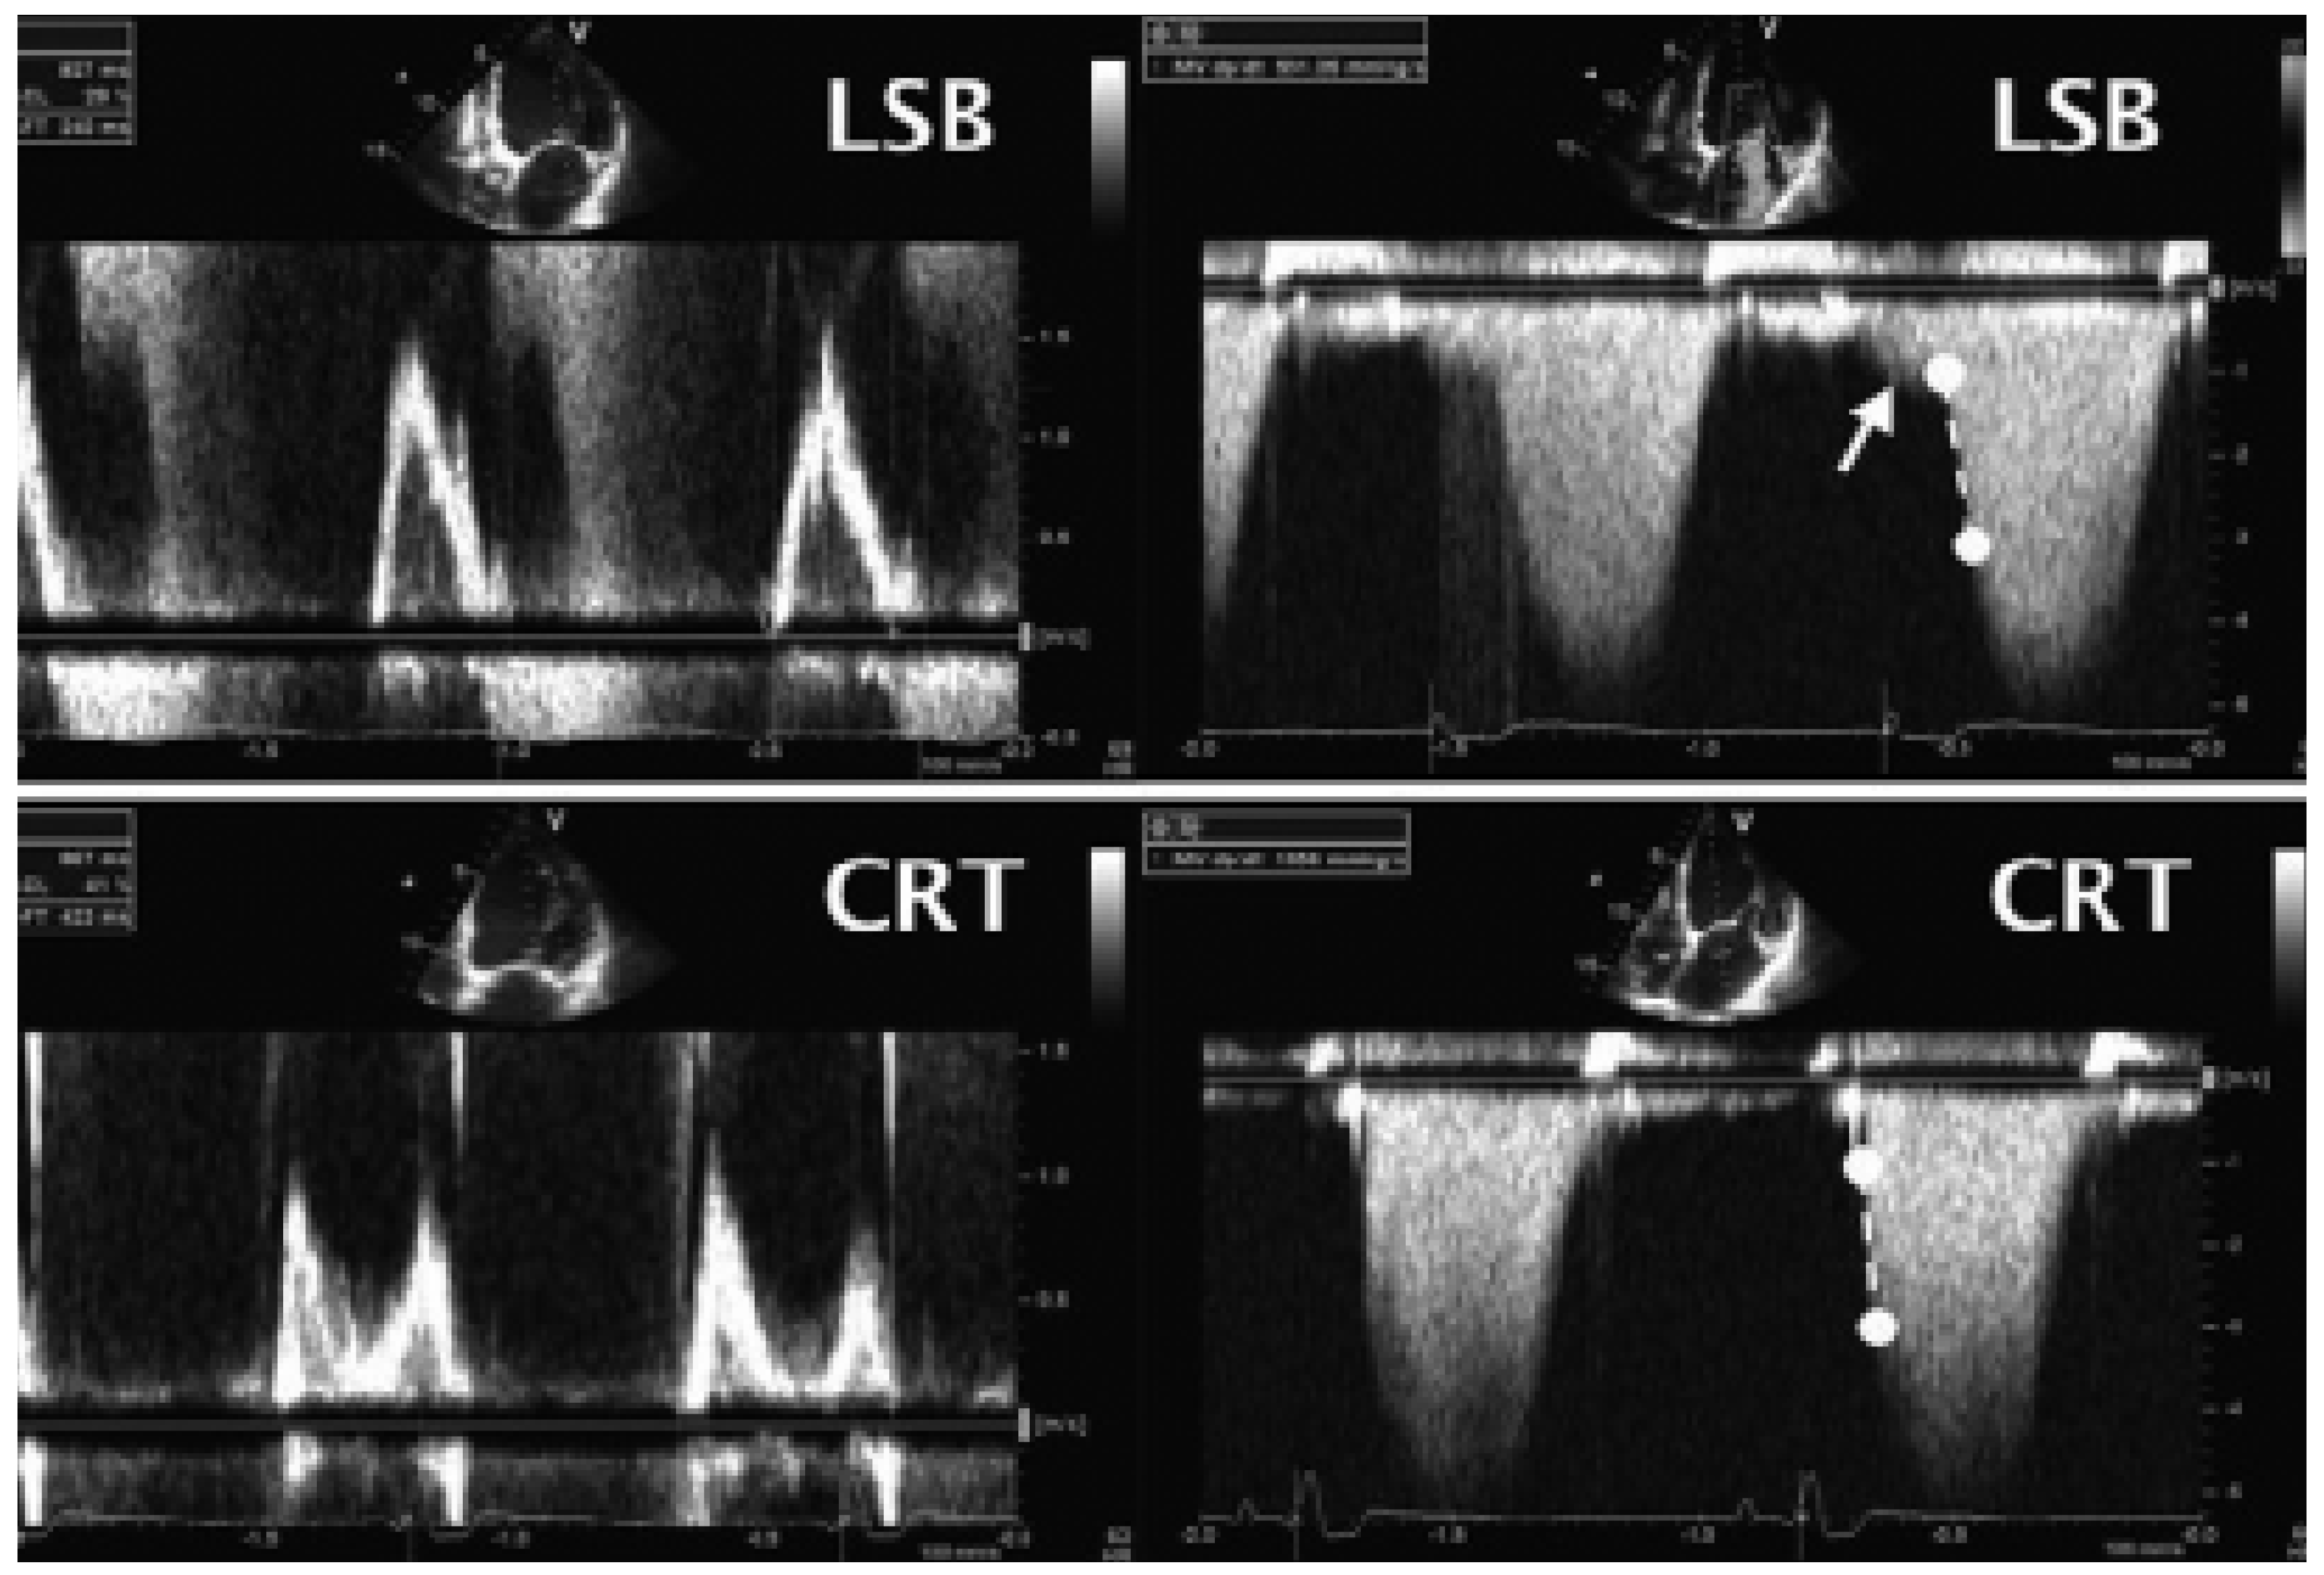

M-Mode

Konventionelle Doppler-Echokardiographie